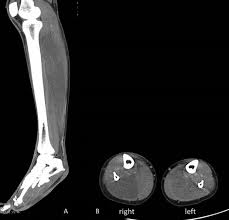

Os médicos perceberam que havia um dano no nervo entre a panturrilha e os pés da paciente, e a diagnosticaram com Síndrome Compartimental. Eles disseram que o problema foi agravado por seu jeans justo.

No caso da mulher australiana, o fato de ela ter passado muito tempo agachada deve ter comprimido seus nervos das pernas e, quando o inchaço começou, o jeans apertado agravou a situação. Ela precisou tomar medicação intravenosa para reduzir o inchaço e só conseguiu andar novamente depois de quatro dias.

O caso foi detalhado no estudo chamado Fashion victim: rhabdomyolysis and tibial neuropathies as a result of squatting in ‘skinny jeans' ('vítima da moda : rabdomiólise e neuropatias tibiais como resultado de se agachar usando um jeans skinny').